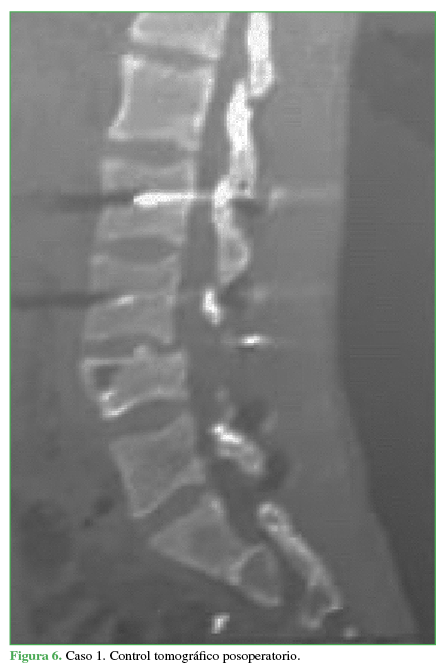

El paciente evoluciona favorablemente con cicatrización de la herida quirúrgica. Comienza con rehabilitación en el posoperatorio inmediato. Se corrige la cifosis segmentaria con medición radiográfica a los seis meses de la cirugía adecuada (Cobb L3-L5 33°, lordosis lumbar 44°, incidencia pelviana 44°, IP-LL 0°, inclinación de la pelvis 18°). El paciente recupera la sensibilidad por completo y evoluciona con una secuela deficitaria parcial motora de raíz L4 izquierda, extensión activa del pie grado 3 (vence gravedad). La TC de control a los dos años muestra la consolidación (Figura 6). Vuelve a montar a caballo (Figura 7 y video ).

Control tomográfico posoperatorio.